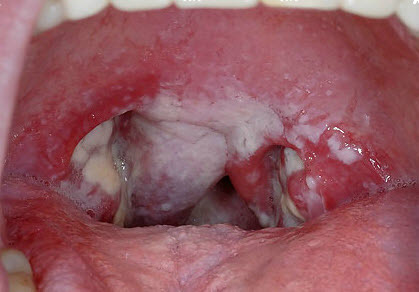

Рис. 28. На фото сочетание флегмонозной и фиброзной ангины. Виден переход воспалительного процесса из лимфоидной ткани в околоминдальную клетчатку.

- острая форма тонзиллита(ангина) – воспаление поверхности миндалин, вызванное стрептококковой или стафилококковой инфекцией, реже – другими патогенными микроорганизмами. Для патологии характерно повышение температуры тела, белый плотный налёт на поверхности миндалин, головные боли, боли в горле, гиперемия задней стенки глотки и увеличение шейных и подчелюстных лимфатических узлов. Для купирования ангины применяются антибиотики от стрептококка в горле, обладающие узким спектром активности. Отдаленные осложнения стрептококковой инфекции могут проявляться поражениям сердца, суставов и т.д.;

Об остром тонзиллите говорят, когда воспаляются небные миндалины. Стрептококк, проникнув в миндалины, вызывает в них воспалительный процесс, характер которого может быть различным (катаральная, фолликулярная, лакунарная, некротическая ангина).

Если барьерная функция тканей, которые окружают миндалины, снижена, то они тоже вовлекаются в воспалительный процесс, в результате чего возникает паратонзиллит (паратонзиллярный абсцесс – острое воспаление в мягких тканях миндалин).

При осмотре миндалин отмечается их значительное увеличение и наличие желто-белого гнойного налета или беловатых пузырьков (фолликулов).